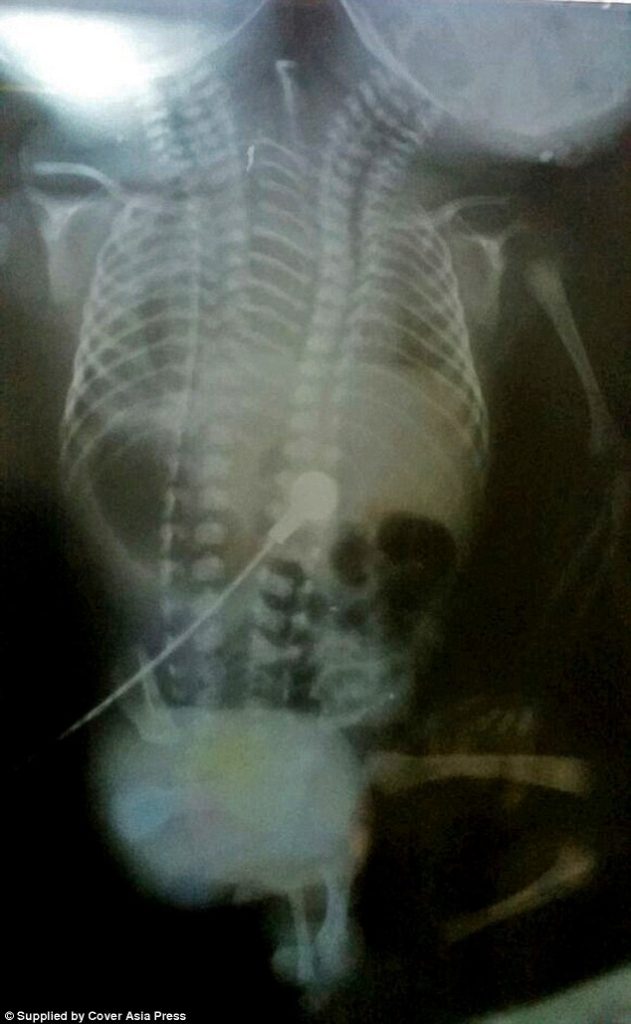

A baby boy with two heads was been born in India and described as a ‘miracle’ by doctors – unfortunately, he died 32 hours later.

According to Daily Mail, the baby boy was born on Monday morning local time to his 20-year-old mother at Jawaharlal Nehru Medical College, in Ajmer, Rajasthan, in northern India, and weighed about 2.5 kilograms (5lbs 7oz).

‘Despite having two pairs of all of their internal organs they were all trapped in one body, with only one pair of arms and legs. You cannot separate such children.’